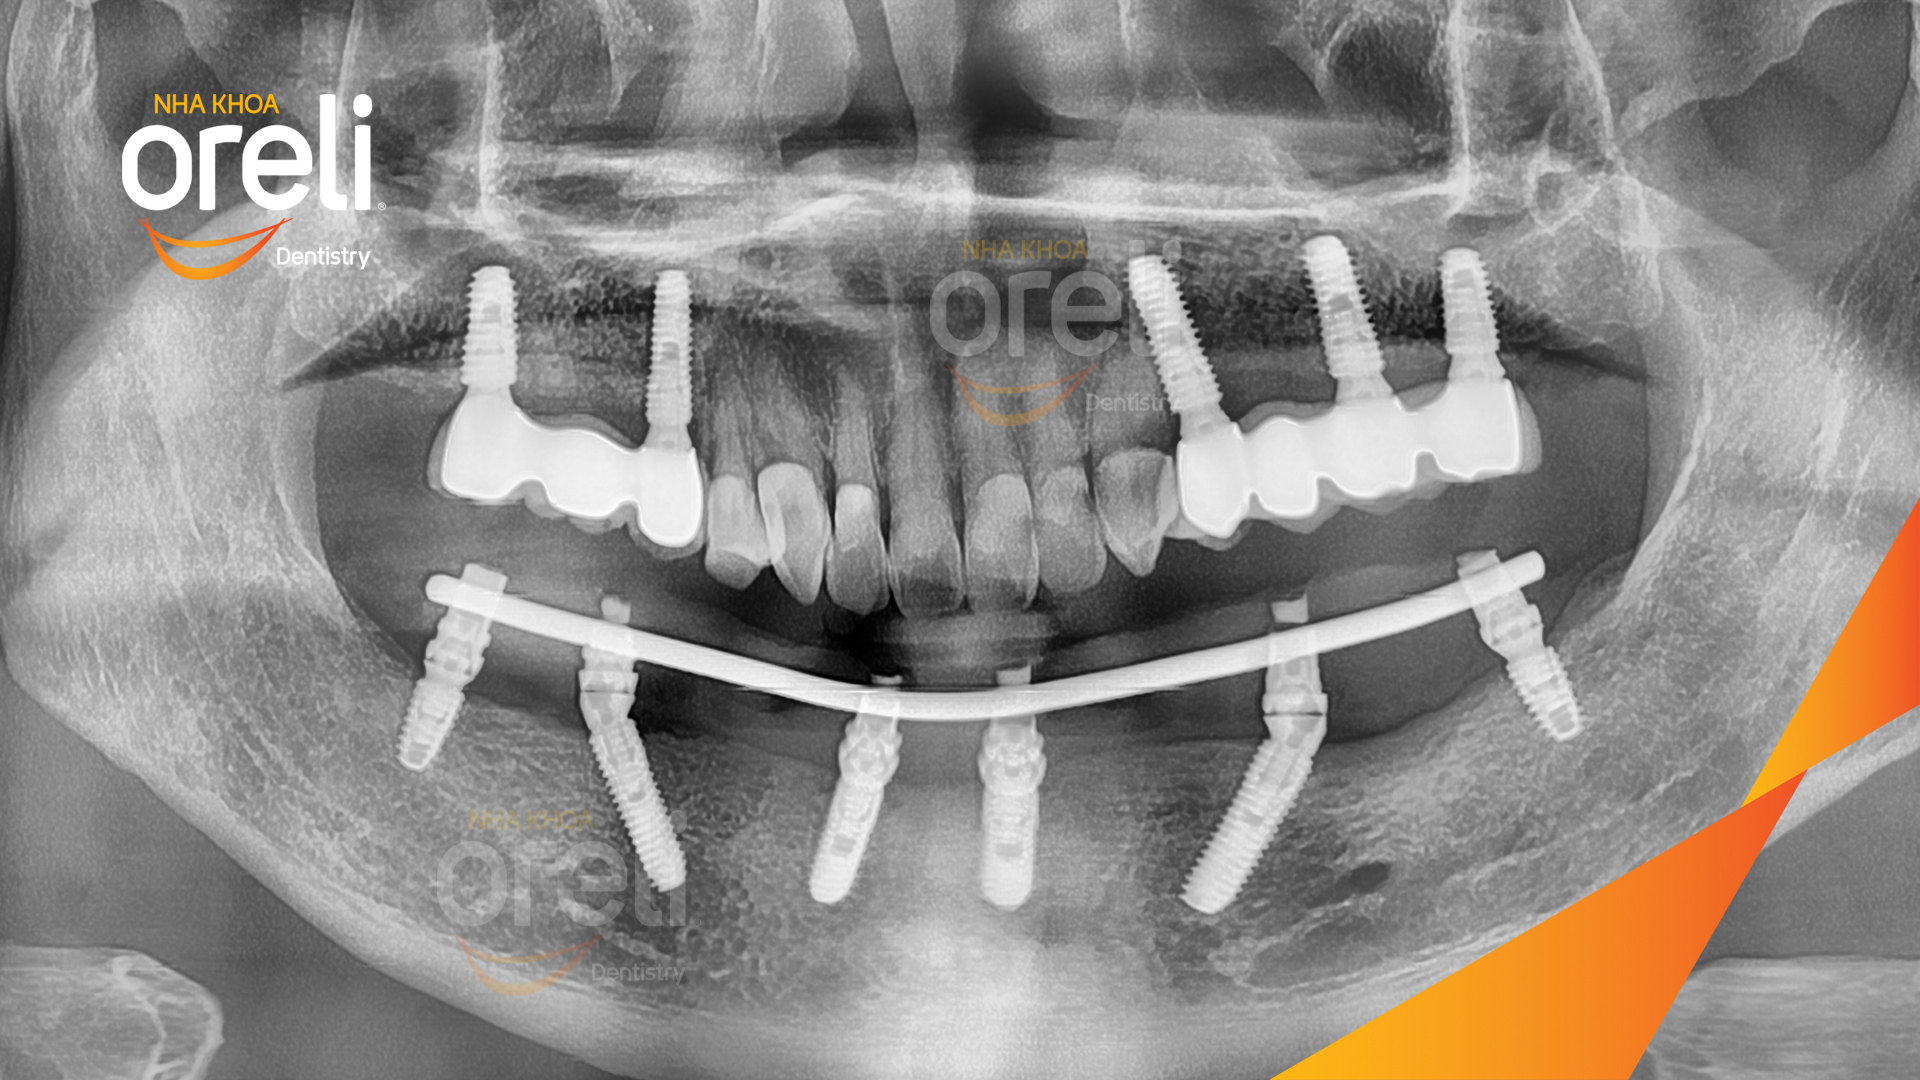

Tình trạng: Mất răng nhai vùng hàm trên và dưới

Giải pháp: Trồng răng implant toàn hàm dưới và vùng răng sau hàm trên

Hình ảnh thực tế